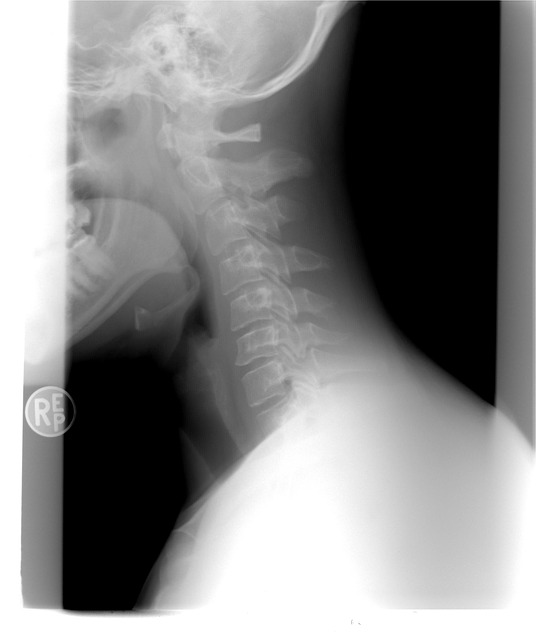

주변을 둘러보면 갑상선에 대한 질병을 흔하게들 많이 들어보셨거나 볼 수 있으실 거예요. 갑상선은 우리 목에 위치해 있는데요. 신진대사에 필요한 갑상선 호르몬을 분비하는 내분비기관을 말합니다.

각종 대사에 필요한 호르몬이기 때문에 갑상선은 매우 중요하죠. 하지만 갑상선 목부음 증상을 느끼시는 분들이 많이 계실 텐데요. 세포성장이 과하게 이루어지거나 할 때 갑상선에 종양이 생겨서 갑상선 목부음이나 이물감을 느낄 수 있습니다.

갑상선 목부음은 갑상선종으로 불리우는데요. 이게 크기가 커지거나 통증이 심해지면 숨을 쉬거나 음식을 삼키는데 불편함이 생겨 일상생활 속에서 많은 불편함을 느낄 수 있다고 해요.